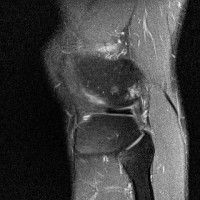

무릎 mri 간단히 봐주실 수 있으시나요 ㅠㅠ

안녕하세요 8년전 십자인대 수술하고 최근 무리한 운동에 무릎 불편감이 생겨서

mri 찍었습니다.

진단결과는 첫 찍은 병원에서 활액막염 이라는 진단을 받았습니다. 혹시 봐주실 수 있으실까요?

올라온 MRI가 단편적이라서 정확한 진단에 어려움이 있지만 십자인대에는 큰 이상이 있지는 않은것 같으며, 무릎관절내 물이 있는 것으로 보아 활액막염의 진단이 맞을 것 같습니다.

하지만 단편적인 영상이기 때문에 촬영병원에서 정확한 판독지 등을 받으시는 것이 좋겠습니다.